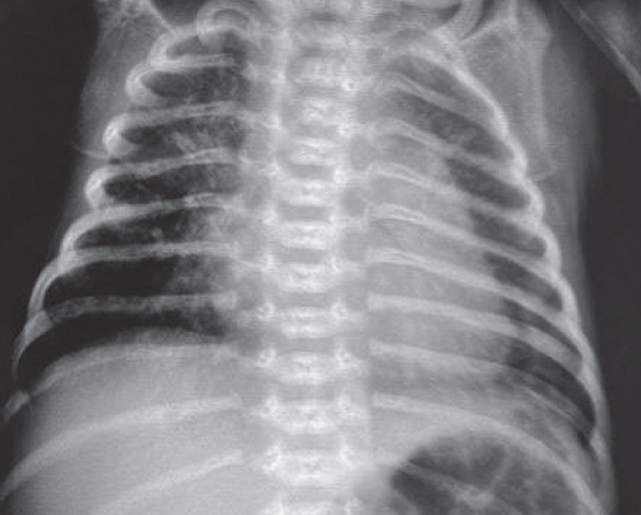

На этом фоне отмечается выраженный положительный эффект в виде увеличения SpO2 с 7–23 до 90 %, на контрольной рентгенограмме сразу после введения порактанта альфа (рис. 3) отмечается незначительное улучшение пневматизации левого легкого, сохраняется свободный воздух в правой плевральной полости.

Рис. 3. Рентгенограмма органов грудной клетки новорожденного после монобронхиального введения сурфактанта

Fig. 3. Chest X-ray of newborn after monobronchial surfactant administration

На контрольной рентгенограмме через 6 ч после манипуляции сохраняются признаки правостороннего пневмоторакса, отмечается неравномерное восстановление воздушности левого легкого. Снизить параметры ВЧО ИВЛ не представлялось возможным. В последующем отмечено прогрессирование явлений дыхательной недостаточности с десатурацией (SpO2 46 %), по анализу газового состава венозной крови отмечается выраженная венозная гипоксемия (рО2 13 мм рт. ст.), гиперлактатемия (6,7 ммоль/л). Сохраняется выраженная артериальная гипотензия, в связи с чем скорость введения адреналина увеличена до 0,2 мкг/(кг · мин), на этом фоне достигнута стабилизация.